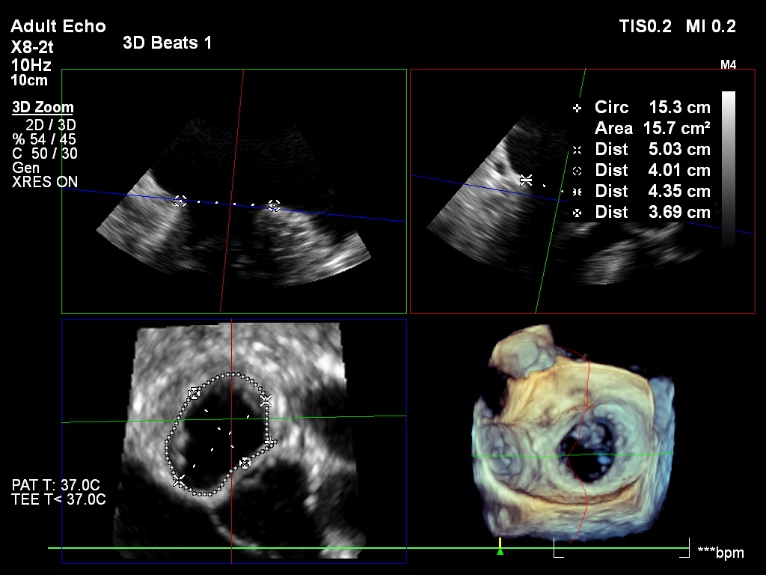

术前瓣口测量

术前CT评估收缩期瓣环

术前CT评估舒张期瓣环

患者男性,86岁,二尖瓣前叶增厚脱垂伴重度反流,双房增大,左室后壁增厚,主动脉瓣钙化伴轻度主动脉瓣反流,重度肺动脉高压伴中重度三尖瓣反流。左心室舒张末内径55mm,收缩末内径29mm。STS评分10.6,属传统外科开胸手术高危人群。